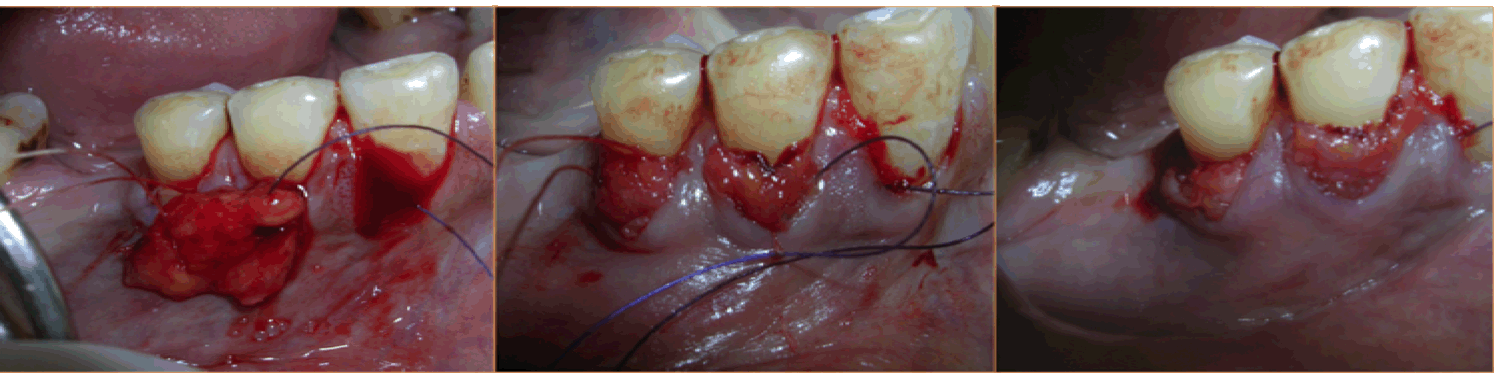

Case 1: A 36-year-old female reported with the chief complaint of sensitivity in lower right posterior teeth. On examination there was Millers Class III recession in relation to 44 and 45 (Figure 1). The width of attached gingiva was found to be inadequate since the tension test was positive. After phase I therapy, a pouch and tunnel technique utilizing a connective tissue graft was planned for root coverage. A sulcular incision was made through each recession area and the tissues gradually undermined including the base of the interdental papilla without the tip and the undermining extended up to the mucogingival junction so as to relax the flap sufficiently to allow placement of the connective tissue graft. Thus gradually a pouch and tunnel was prepared connecting the recipient sites for placement of the graft (Figure 2). The connective tissue graft was harvested from the palate using Liu's Class 1a incision (Figure 3). This graft was then placed using a technique described by Zabaluigi et al. where two resorbable sutures of different colors were placed, one on either side of the graft. Using these sutures, the graft was gradually manipulated into the pouch and through the tunnel to cover the adjacent recipient sites. Once the graft was completely inside the tunnel, it was positioned coronal to the cemento-enamel junction. The ends were sutured with a simple square knot (Figure 4). A periodontal pack was placed both at the recipient site as well as the donor site using an acrylic stent for the palatal placement.

Figure 2: Pouch and tunnel preparation (Case 1).

Figure 4: The graft placed into the tunnel and sutured.